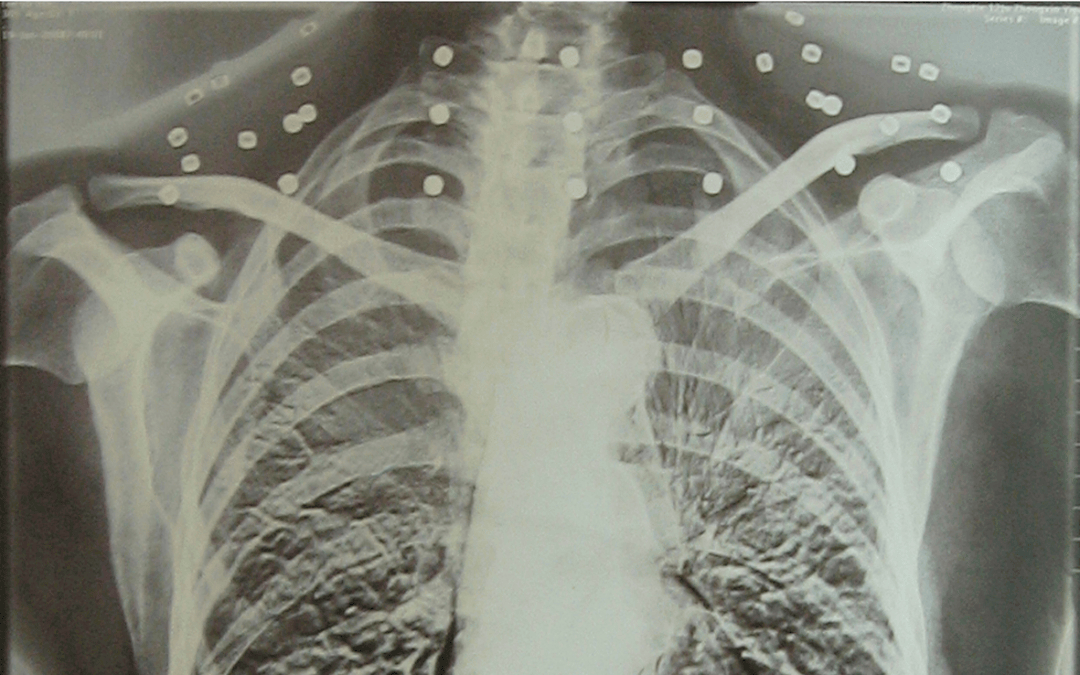

这张照片

是今年82岁的吴以先老人

拍摄的一张CT照

但实际上是

吴以先的颈部和腹部

共分布着33枚弹片

他体内的弹片都没有取出

身体留有弹片的位置就有痛感

但吴以先不考虑取出弹片

在他看来

这是他与战友并肩作战的见证

是他的勋章

与吴以先身上那33枚弹片

一起永远烙印在他心中

33枚“军功章”

是一名军人的光荣